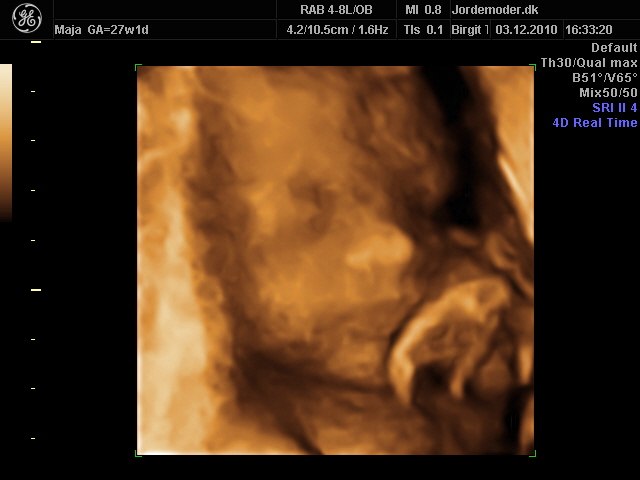

billede 8 - 27+1 3d